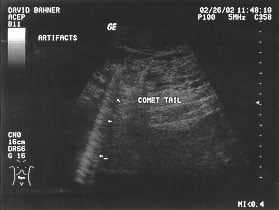

Artifacts - comet tail